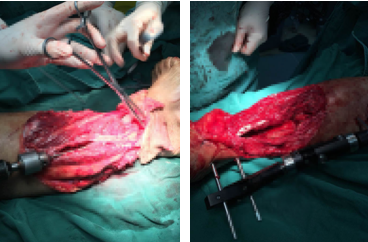

第二次手術(shù)中

第二步:2017年12月25日,在腰硬麻醉下行右小腿第二次清創(chuàng)以及VSD更換術(shù)。對前期保留觀察的皮膚組織進(jìn)行處理,對明確的壞死組織進(jìn)行清理,手術(shù)時間1小時左右。同時也可看到,在VSD的作用下,患者的創(chuàng)傷部位已經(jīng)長出了一些新鮮的肌肉組織。

第四步:2018年1月25日,手術(shù)到了最為關(guān)鍵且難度最大的一步——皮瓣的轉(zhuǎn)移成形修復(fù)+取大腿皮植皮術(shù)。醫(yī)生從患者的腹部和同側(cè)大腿分別取出8*15CM左右的兩塊皮瓣(皮膚帶著肌肉、脂肪、血管等),覆蓋在患者的右小腿創(chuàng)傷部位。然而,為了讓轉(zhuǎn)移過來的皮瓣能夠存活,這不僅是簡單的皮膚縫合,更關(guān)鍵的是神經(jīng)、血管的修復(fù)吻合。在顯微鏡下,醫(yī)生巧施妙手,精雕細(xì)琢,將粗細(xì)不過1毫米左右的神經(jīng)、血管,分別接到血管缺損的部位。多名醫(yī)護(hù)人員默契配合,持續(xù)奮戰(zhàn)11個小時左右,終于成功完成了這場高難度的手術(shù)。